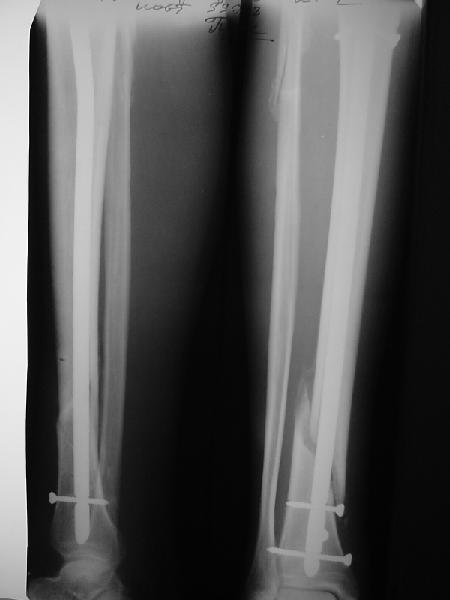

Как мне показать пример? Фото стоящего на одной оперированной конечности пациента? O! Пример, подвигнувший нас на некоторое изменение технологий. Пациент этот ходил с полной нагрузкой вопреки рекомендациям. В качестве подтверждения - сломанный проксимальный статический винт к 1 мес., а к 2 мес. - все остальные. Сейчас мы перешли на более fool-proof остесинтез.